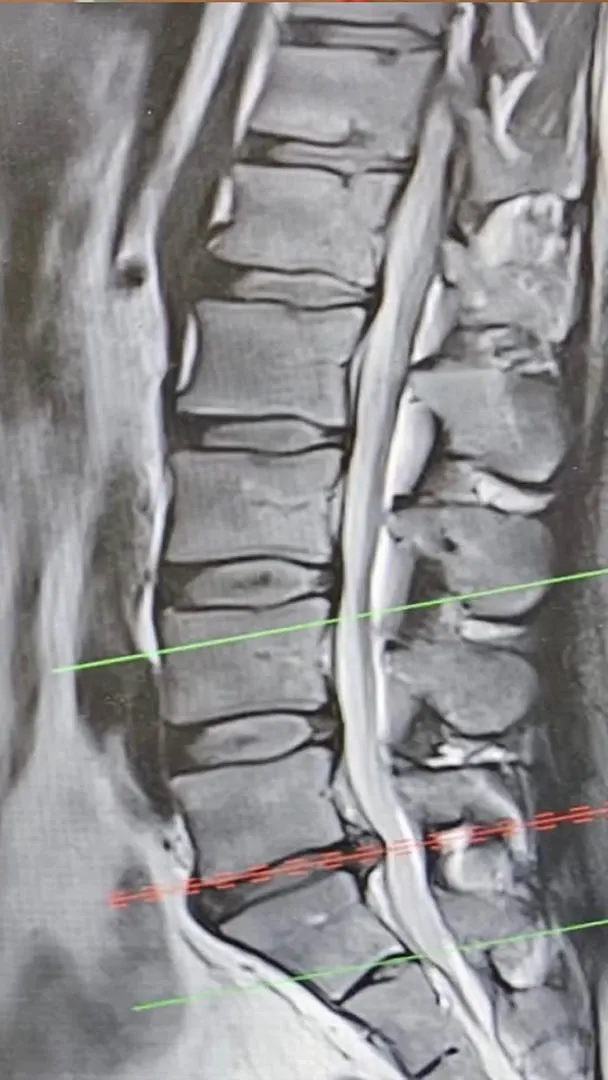

Turek se vyjádřil i ke svému zdravotnímu stavu. Upřesnil, že má „poměrně drsně“ vyhřezlou ploténku. V neděli byl podle svých slov na magnetické rezonanci. Vysvětlil, že před několika dny prakticky přestal chodit. Dostával infuze a silné léky na bolest. S ploténkou měl potíže už v minulosti.